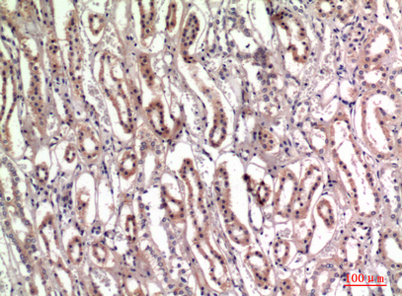

Product name: Tenascin-C rabbit pAb

Dilutions: Western Blot: 1/500 - 1/2000. IHC-p: 1:100-1:300. ELISA: 1/10000. Not yet tested in other applications.